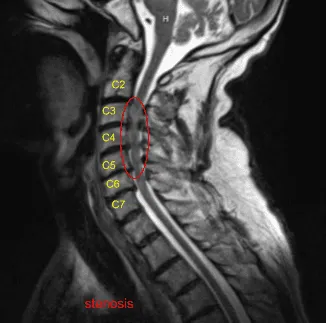

An MRI was done and found to have severe stenosis on C3-4 with moderate to severe stenosis on C4-5 and C5-6. Dr. Mariwalla and I discussed treatment options and the patient opted for surgical management. We discussed the need for anterior cervical discectomy and placement of cages as well as screws.